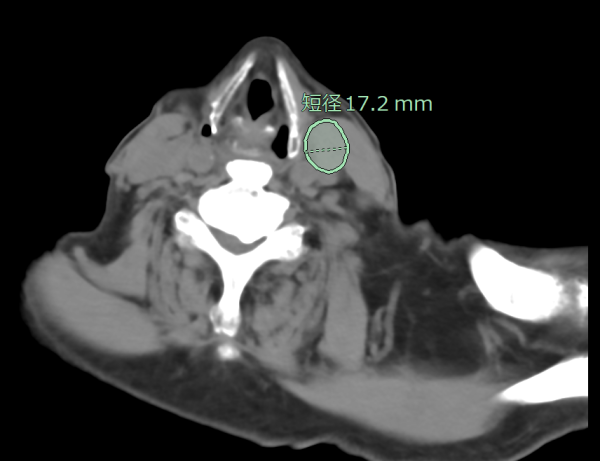

CT頸部・腹部リンパ節抽出

リンパ節は全身に存在しており、想定外の箇所が腫大することもあるため、読影に大きな負担がかかっている。従来、CT画像(造影・非造影)において、縦隔・腋窩リンパ節の抽出が可能だったが、今回、頸部・腹部(大動脈周囲、骨盤部)でもリンパ節の抽出ができるように対象範囲を拡充した。縦隔・腋窩だけではなく、頸部・腹部も含めた箇所における腫大傾向のリンパ節を拾い上げ、自動で短径計測を行う。癌の転移検索の支援に繋がることが期待される。